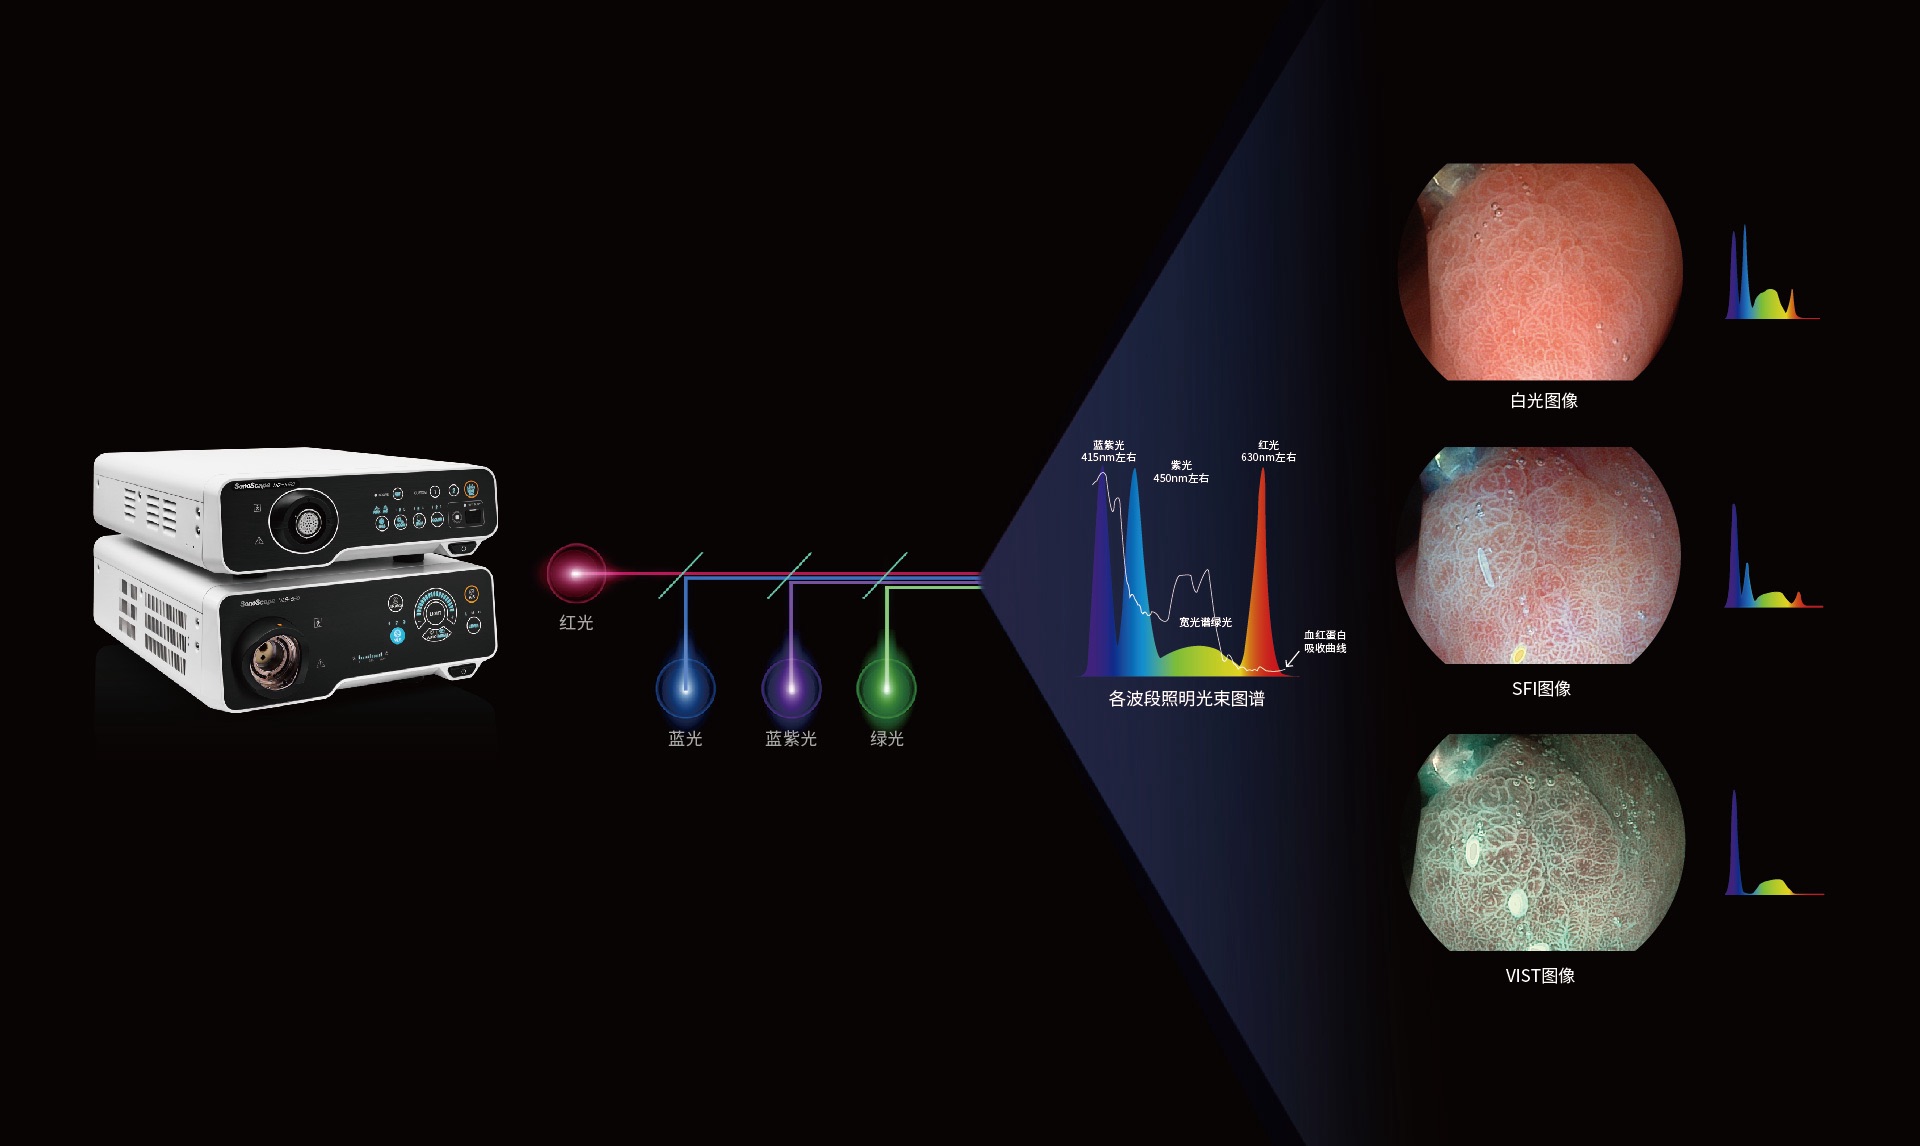

Spectral Focused lmaging, SFI

图像具有高亮度、高黏膜血管颜色对比度的特点,且不改变粘液、食物残渣、粪便的基本颜色,可在中远景下进行观察,助力消化道早期疾病的诊断。

Versatile Intelligent Staining Technology, VIST

强调浅层黏膜结构的同时,保证照明亮度和提升浅层微血管与中层血管颜色对比度,病变边界更清晰。

采用光路合束技术,光谱自由度高,实现了更丰富的照明模式,染色模式SFI及VIST,从远景到近景,助力消化道早期疾病诊断。